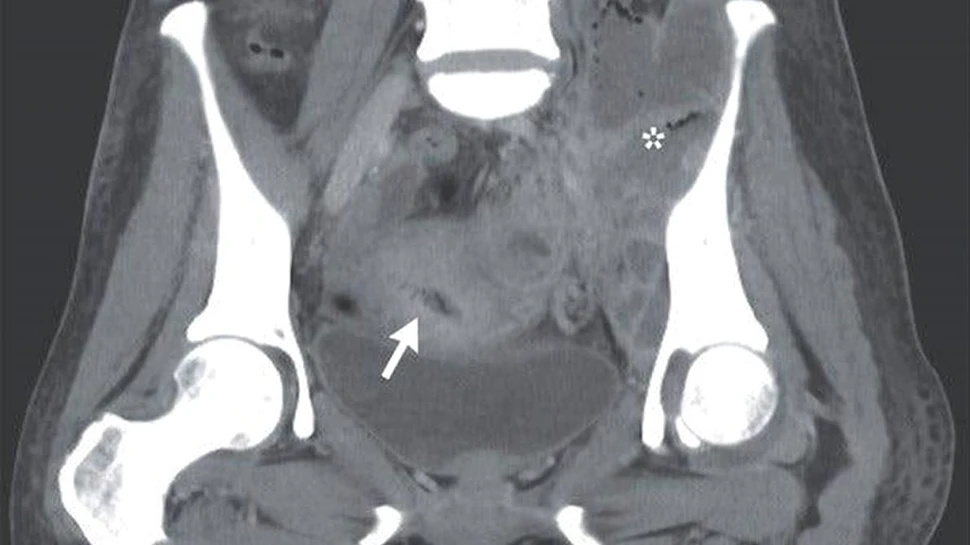

Credit foto: Noriko Arakaki si Yusuke Oshiro - NEJM

Un examen fizic a dezvăluit un nodul în partea de jos, în stânga abdomenului, care producea durere la atingere, astfel încât medicii au cerut efectuarea unui CT și prelevarea de sânge.

Examinarea la computerul tomograf a arătat o serie de abcese în jurul steriletului care se afla încă în uter. Rezultatele analizelor de sânge au confirmat infecția, deoarece numărul de celule albe din sânge – care combat infecțiile – era crescut. Infecția se răspândise dincolo de pelvis și în articulația șoldului stâng.